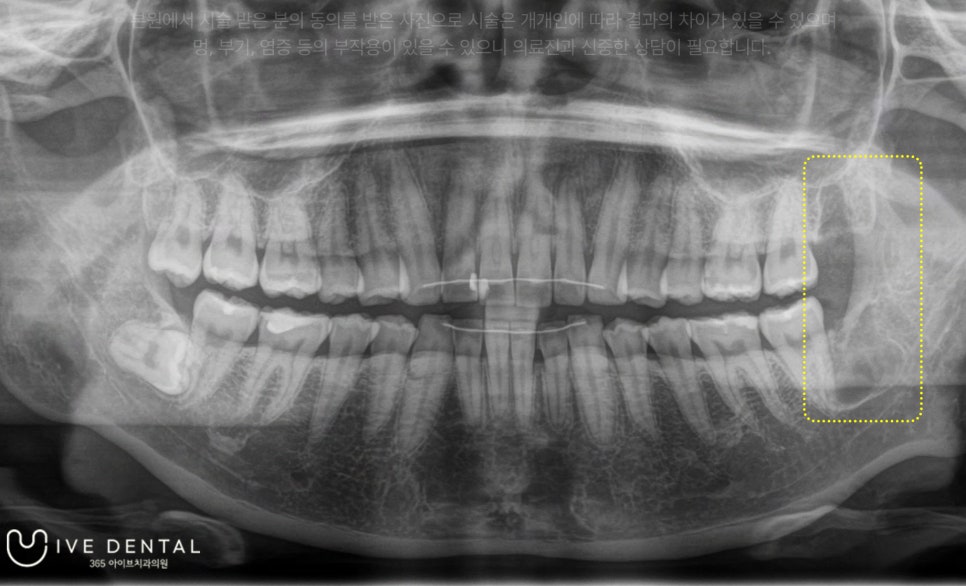

저희 아이브치과에서는 양쪽 사랑니 4개 모두 하루에 발치 진행이 가능하지만, 환자분께서는 왼쪽 사랑니부터 발치를 원하셨습니다.

​마취 후 바로 전주사랑니발치를 진행하였고요

환자분을 골치 아프게 하던 사랑니가 깔끔히 제거된 것이 보이시나요?

매복사랑니와 돌출 사랑니 발치에 총 걸린 시간은 5분 내외입니다.

이렇듯 전주사랑니발치를 진행하는 아이브치과에 내원하시면, 간단하고 빠르게 골칫덩이였던 사랑니를 제거하실 수 있습니다.